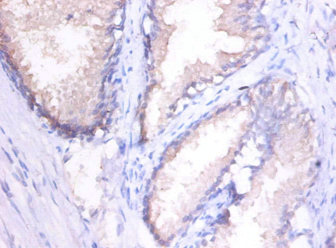

• Immunohistochemistry of paraffin-embedded human placenta tissue using CSB-PA07009A0Rb at dilution of 1:100